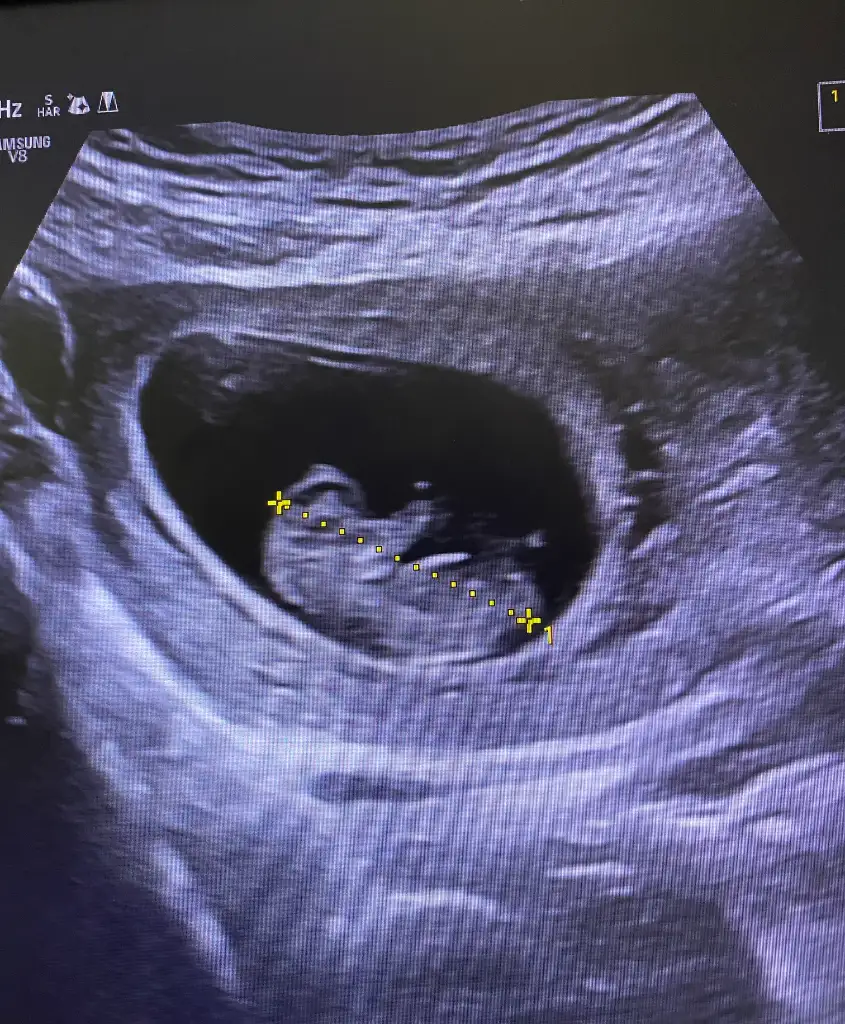

Kızlarrr tahmin edecek var mı cinsiyeti. 10 haftalığım ❤️🌸

• IMG_5667.webp

IMG_5667.webp

95,5 KB · Görüntüleme: 63